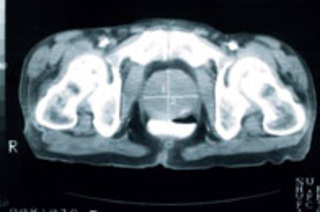

Image: iStockphoto